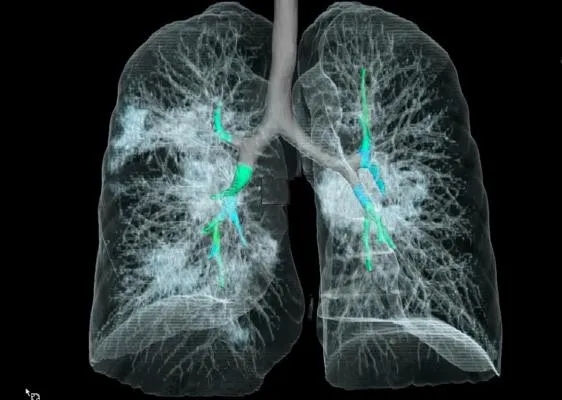

采用CT三维成像技术,

暴露在人们裸眼眼前,

到处是斑片状磨玻璃影(见下图)。

01-4.webp

图片来自Radiology

来自Internet图片搜索